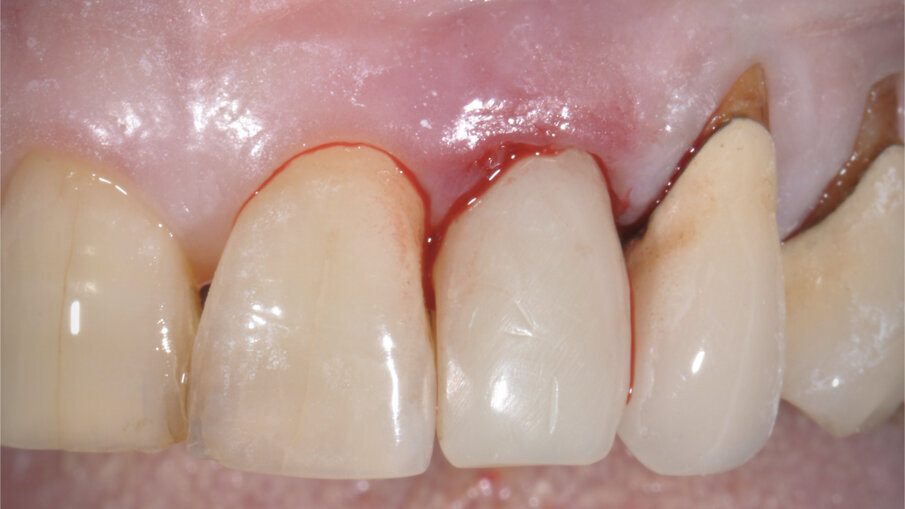

Il poter disporre di una tipologia di fixture estremamente orientata al conseguimento di elevati valori di stabilità primaria ha costituito un ulteriore elemento a favore di questa scelta. La paziente è stata sottoposta ad un trattamento preliminare a cielo coperto mediante levigatura radicolare. Il giorno dell’intervento, sotto profilassi antibiotica, è stata eseguita l’estrazione in maniera micro-traumatica e la rimozione mediante curettage dei tessuti infiammatori presenti. Non è stato eseguito un lembo di accesso, ma è stata verificata la presenza di tessuto osseo in sede vestibolare (Fig. 3).

Fig. 3_Alveolo post-estrattivo.